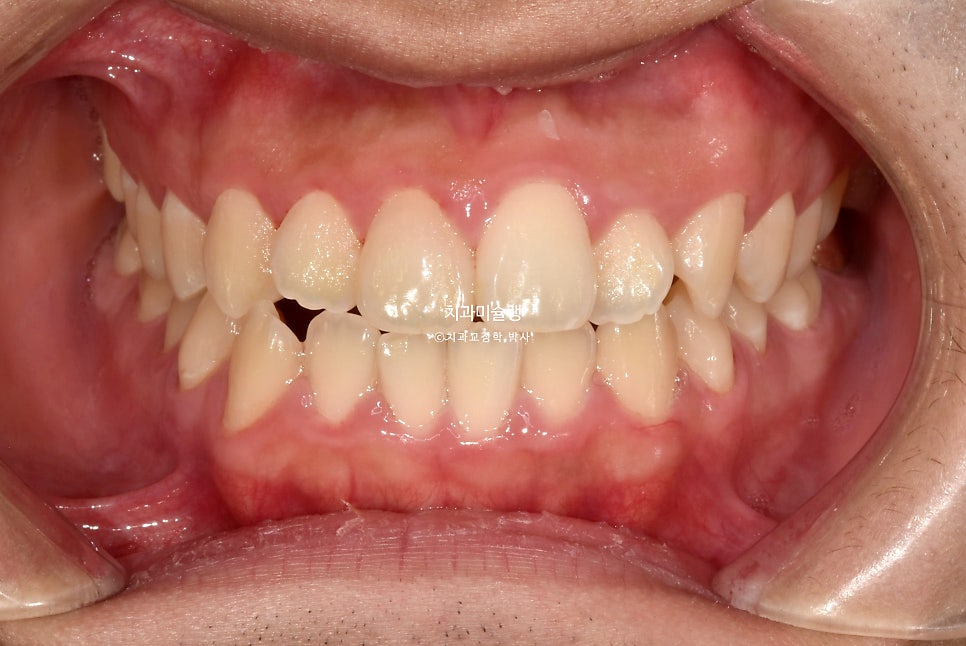

돌출입과 거미스마일(잇몸미소) 인비절라인 발치교정 사례

오늘은 돌출입과 거미스마일 (잇몸미소)가 있는 경우의 인비절라인 발치교정 이야기를 해보겠습니다.

24년 봄, 교정치료를 위해 내원한 환자분 입니다.

중심선 불일치, 반대교합, 덧니 등이 보입니다.

어금니 교합은 좋지만

입이 잘 안다물어질 정도의 돌출이 있습니다. 돌출때문에 입이 잘 안다물어지고 자꾸 벌어지는 증상을 입술부전증 이라고 합니다.

웃을때 잇몸도 많이 보이는 편.